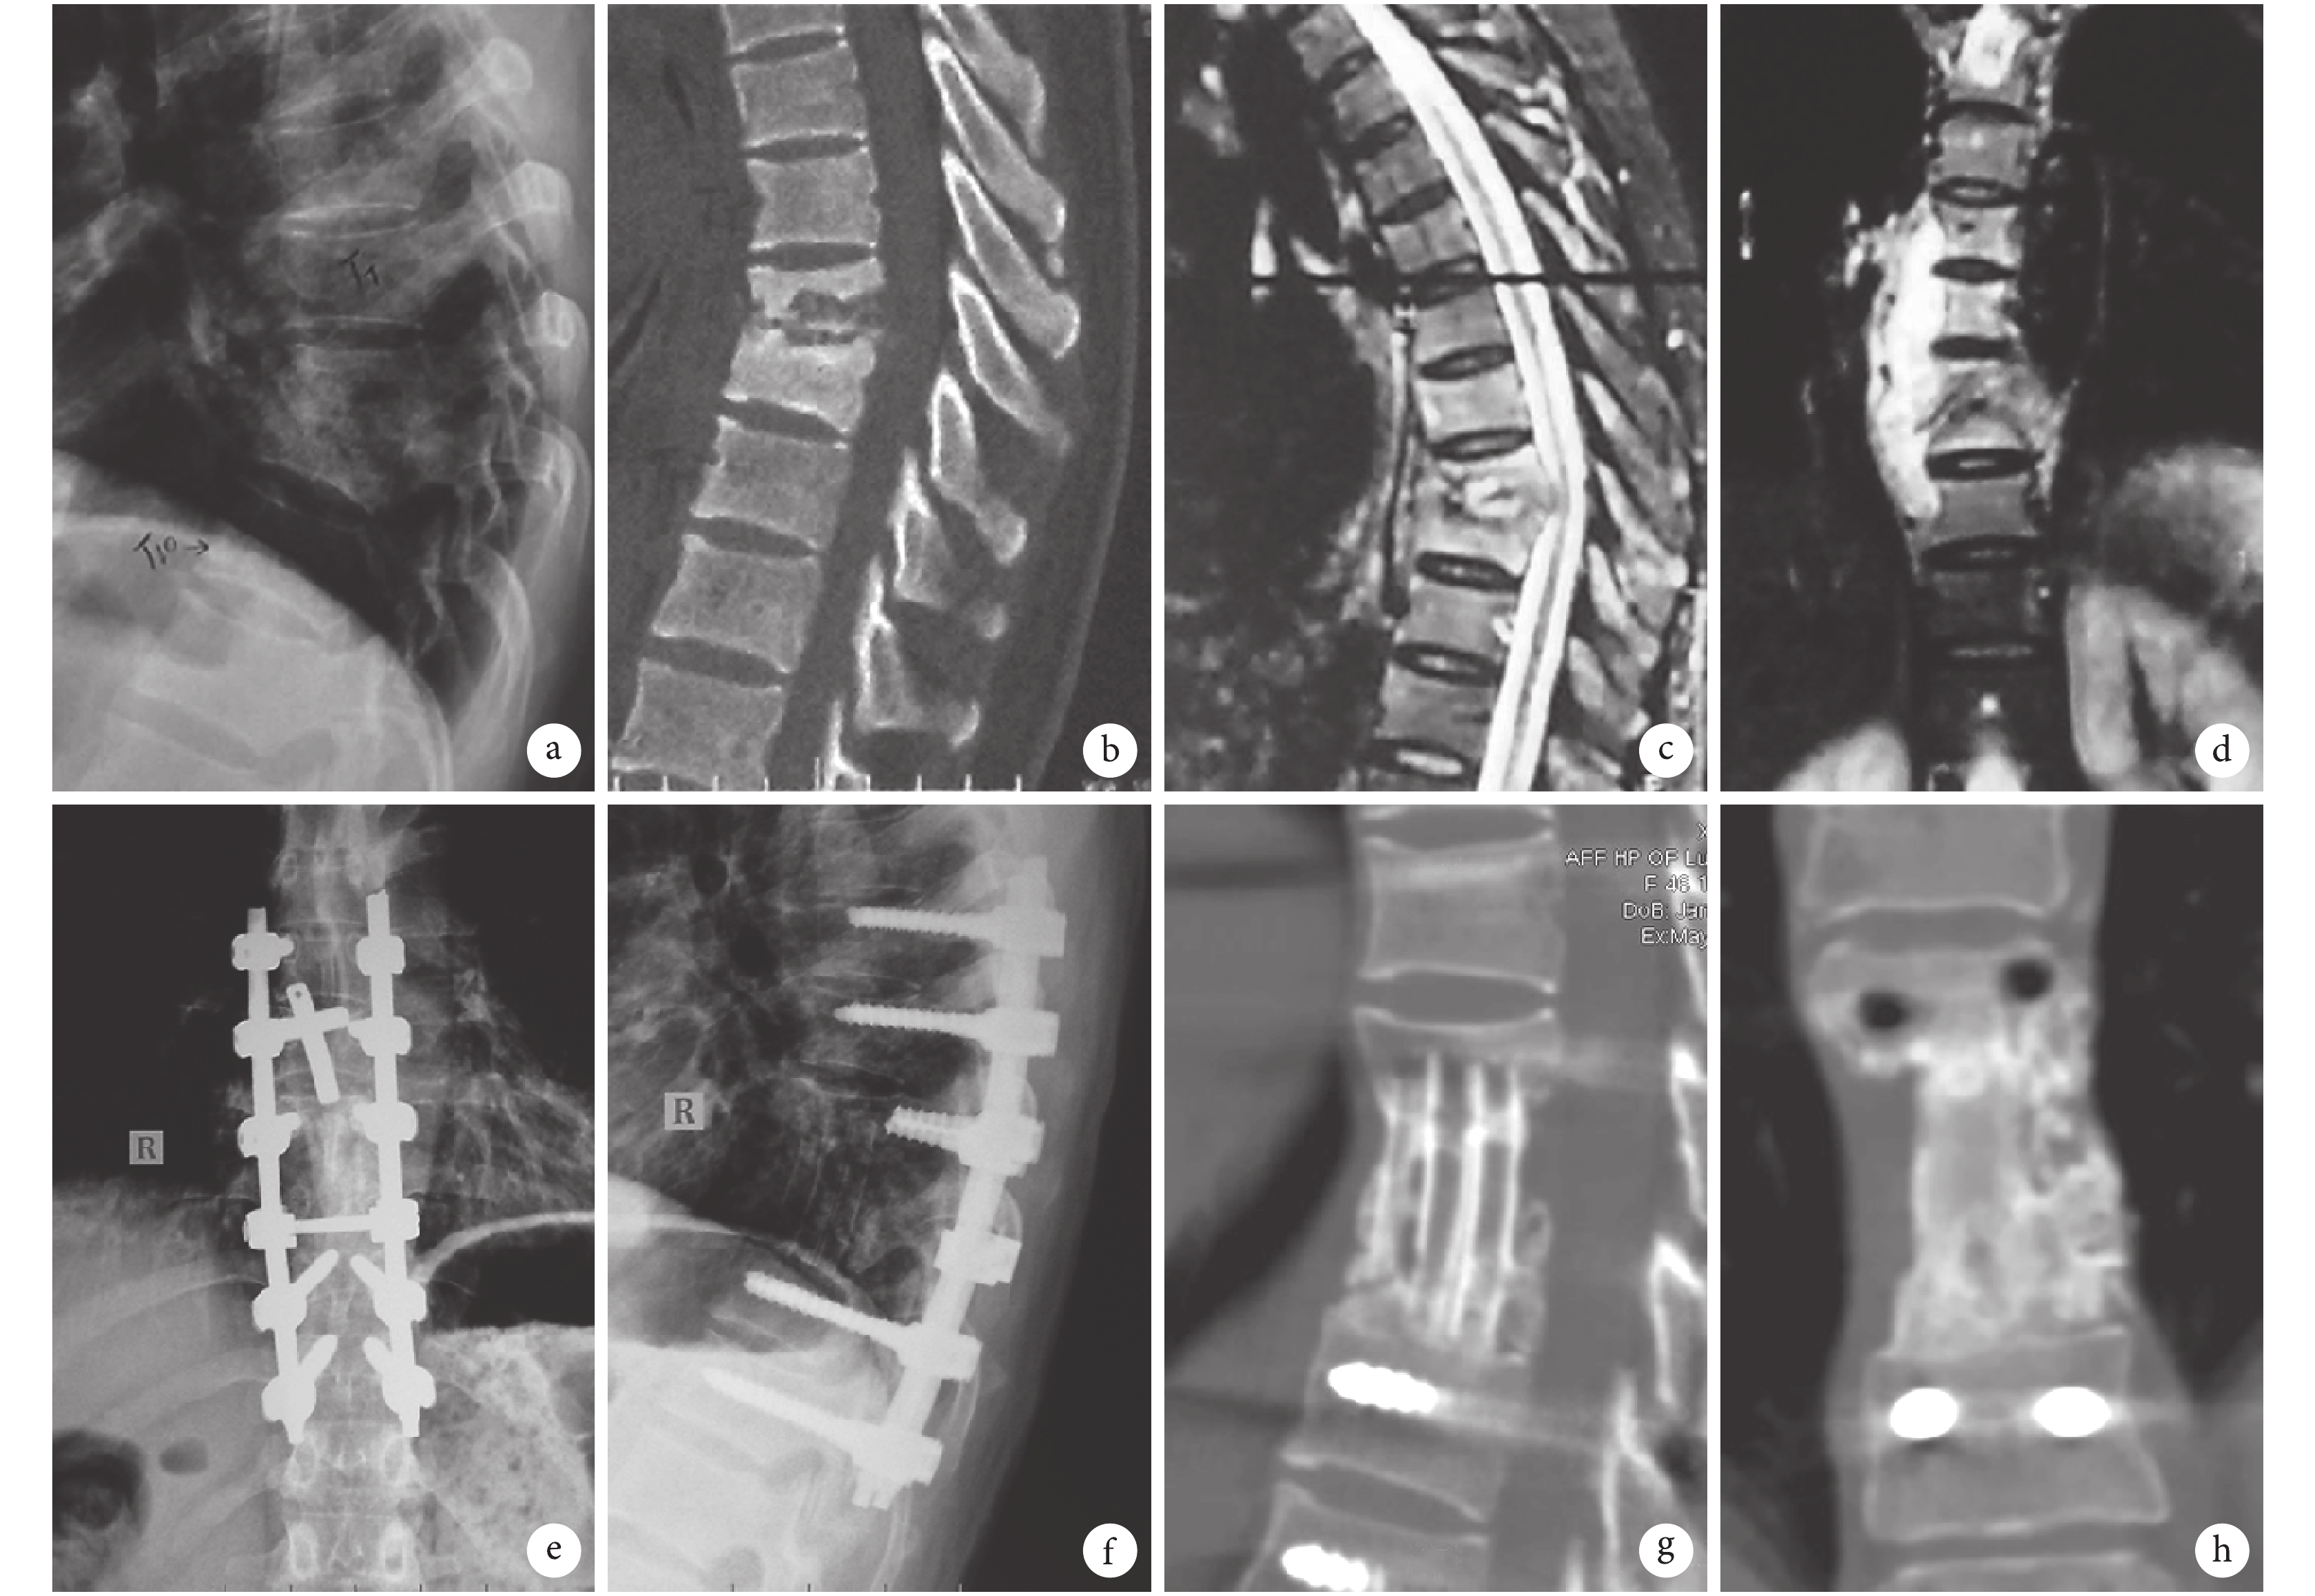

a. 術前側位 X 線片示 T8、9 椎體間隙狹窄;b. 術前 CT 示 T8、9 椎體破壞,椎體間隙狹窄;c、d. 術前 MRI 示 T8、9 椎體高信號,T7~11 椎旁梭形膿腫形成;e、f. 術后 3 個月正側位 X 線片示椎體后凸畸形糾正,內固定物位置良好,捆綁肋骨支撐體位置良好;g、h. 術后 1 年 CT 三維重建示捆綁肋骨與上下椎體完全融合

Figure2. A 59-year-old female patient with T8, 9 tuberculosis, using autologous bundled multi-segment rib graft reconstruction for bone defects after thoracic spinal tuberculosis debridementa. Lateral X-ray film before operation, showing T8, 9 intervertebral space stenosis; b. CT before operation, showing T8, 9 vertebral body destruction with intervertebral space stenosis; c, d. MRI before operation, showing T8, 9 vertebral bodies high signal and paravertebral abscess at T7-11; e, f. Anteroposterior and lateral X-ray films at 3 months after operation, showing kyphosis deformity corrected without displacement of rib graft and instrumentation; g, h. CT three-dimensional reconstruction at 1 year after operation, showing complete fusion of bundled rib with vertebral body up and down